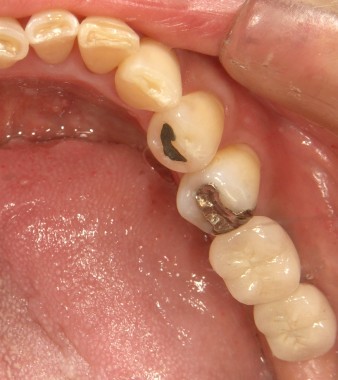

インプラントの術前・術後 Nさん